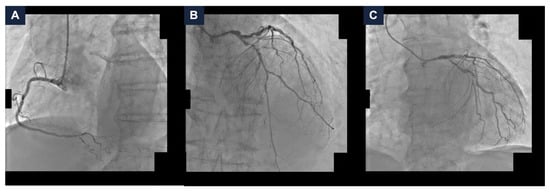

The final angiographic result was satisfactory, with a Thrombolysis in Myocardial Infarction (TIMI) grade 3 flow (Figure 3 and Video S2). The hemodynamics remained stable, so the MCS device was removed at the end of the procedure, with no vascular access complications. A total of 40 mL of Iodixanol 270 mg I/mL was administered. Post-procedurally, the eGFR reached 13 mL/min/1.73 m2. The patient was managed with intravenous hydration. The serum potassium did not exceed 5.0 mEq/L and the urine output remained stable. After a few days, the kidney function returned to baseline values (eGFR 27 mL/min/1.73 m2). No in-hospital adverse events occurred. The patient remained free from angina at the one-year follow-up [6].

Figure 3.

Final complex high-risk indicated procedure result. Final coronary angiography demonstrating a good final result with Thrombolysis In Myocardial Infarction grade 3 flow in spider (panel A), caudal (panel B), and cranial (panel C) views.